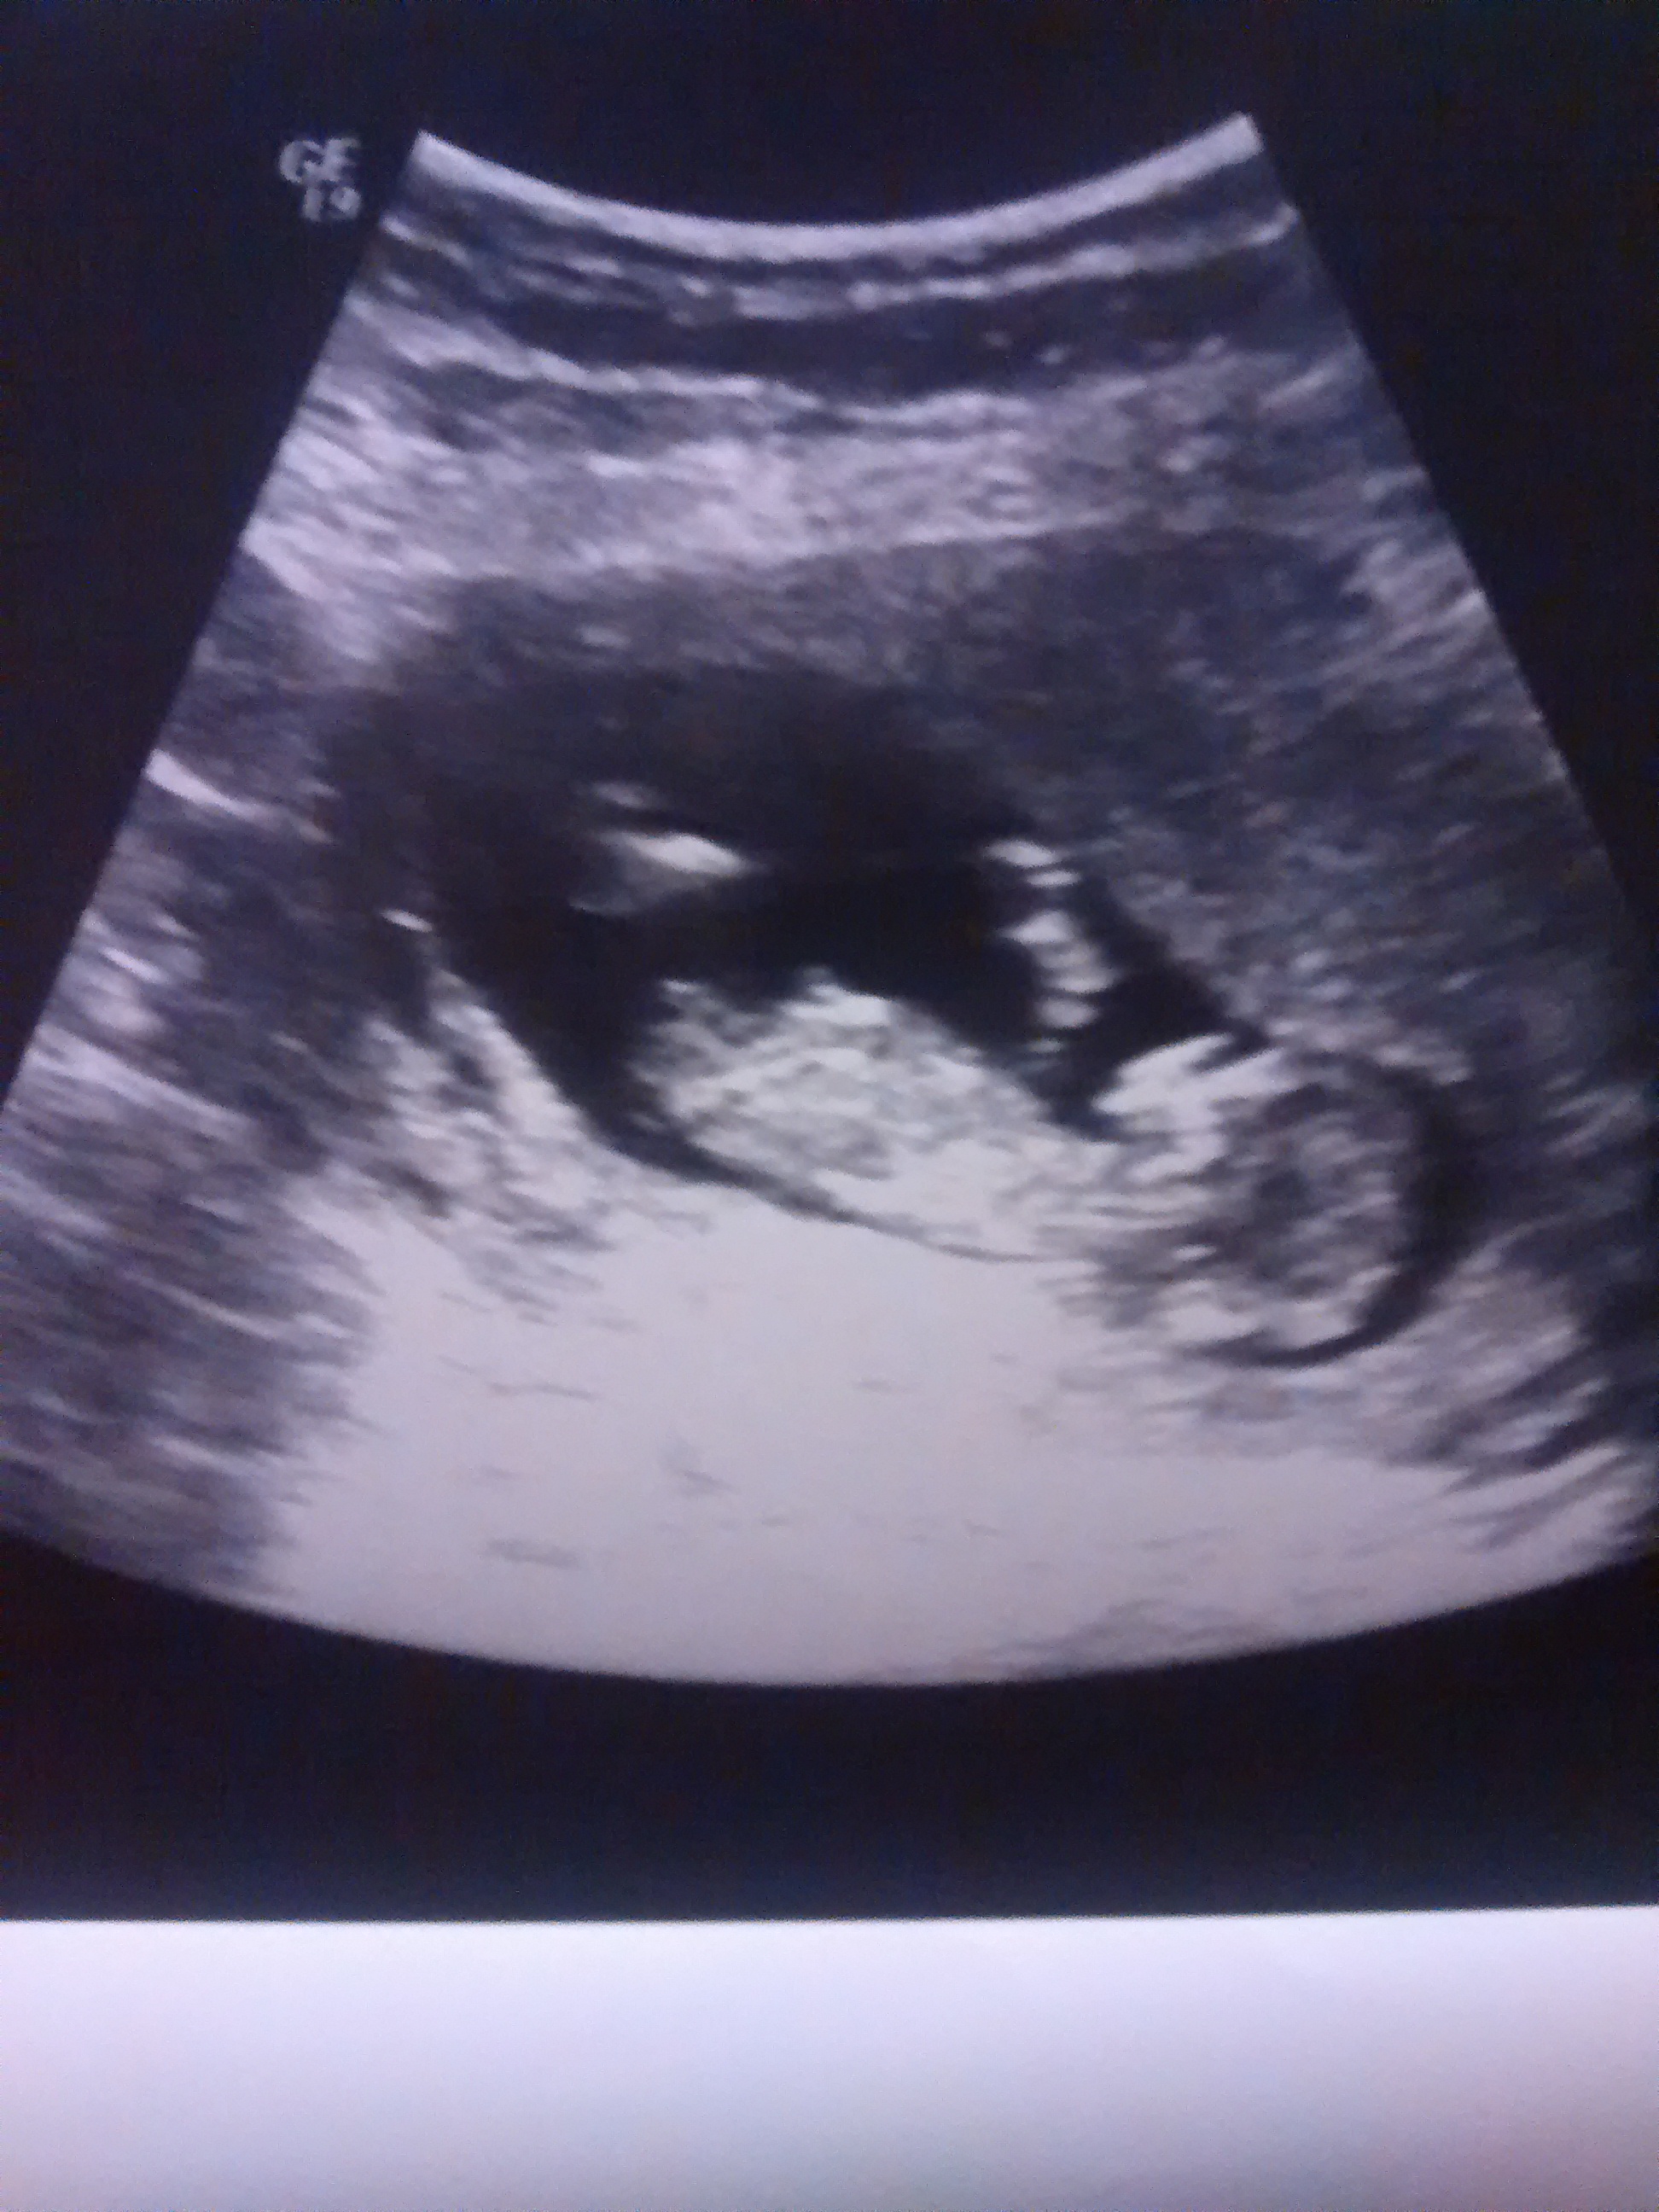

Good chance of hearing pink x

Pretty sure that's a boy.

Thinking blue

IN THIS IMAGE IT LOOKS LIKE A BOYS PARTS BUT AGAIN, IM NOT AN EXPERT. ANY ADVISE

strong girl lean here too

Looks boyish to me :)

Looks like a girl nub to me

Girl guess from me.

I'm thinking boy.

I'm leaning toward girl.

Boy